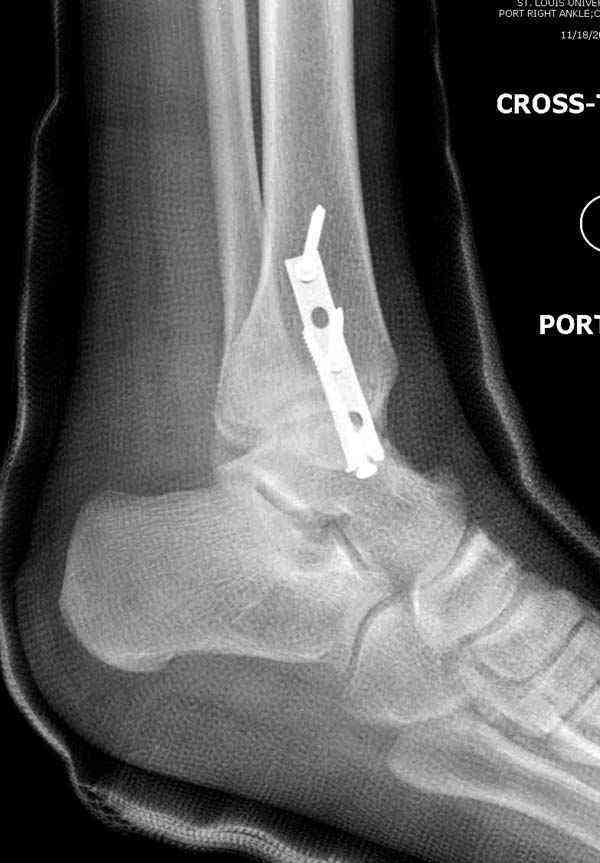

Во всех руководствах АО имеется описание техники применения низкопрофильных пластин 1/3 трубки, которые могут быть применены для фиксации наружной лодыжки. Фиксацию проводят кортикальными 3.5 мм шурупами, и если дистальная фиксация недостаточная, тогда усиливают конструкцию созданием hook plate. Сгибая конец пластины на последнем отверстии, внедряют его в дистальный отдел, и тем самым создается дополнительная фиксация.

Современные преконтурированные пластины не имеют таких недостатков, и разделяются на правые и левые, а также на латеральные и задние. Множественные дистальные шурупы 2.7 мм уменьшают подкожное раздражение, и такой имплант можно оставить на долгий срок без удаления.

Для молодых достаточным бывает обычная лодыжечная пластина без блокировки, и только у пожилых с остеопорозом лучше взять полиаксиальные пластины с угловой стабильностью.

Здесь несколько частных случаев: перелом голеностопа со сравнительными снимками и разрыв синдесмоза, а также медиальная Hook пластина.